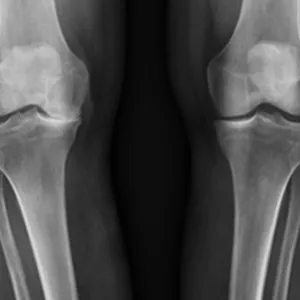

Dei nedslitte leddflatene skaper kraftig irritasjon i leddet. Dette fører til smerte og hevelse. Hevelsen skuldast at det irriterte kneleddet danner meir leddvæske enn normalt. Etter kvart som artrosen auker, kan sjølve leddet forandra seg. Det dannar seg beinpåleiringar og forkalkningar, ein kan bli hjulbeint eller kalvbeint. Slitasjen må ikkje nødvendigvis omfatta heile kneet. Ofte vil berre delar av leddet utvikla slike forandringar.